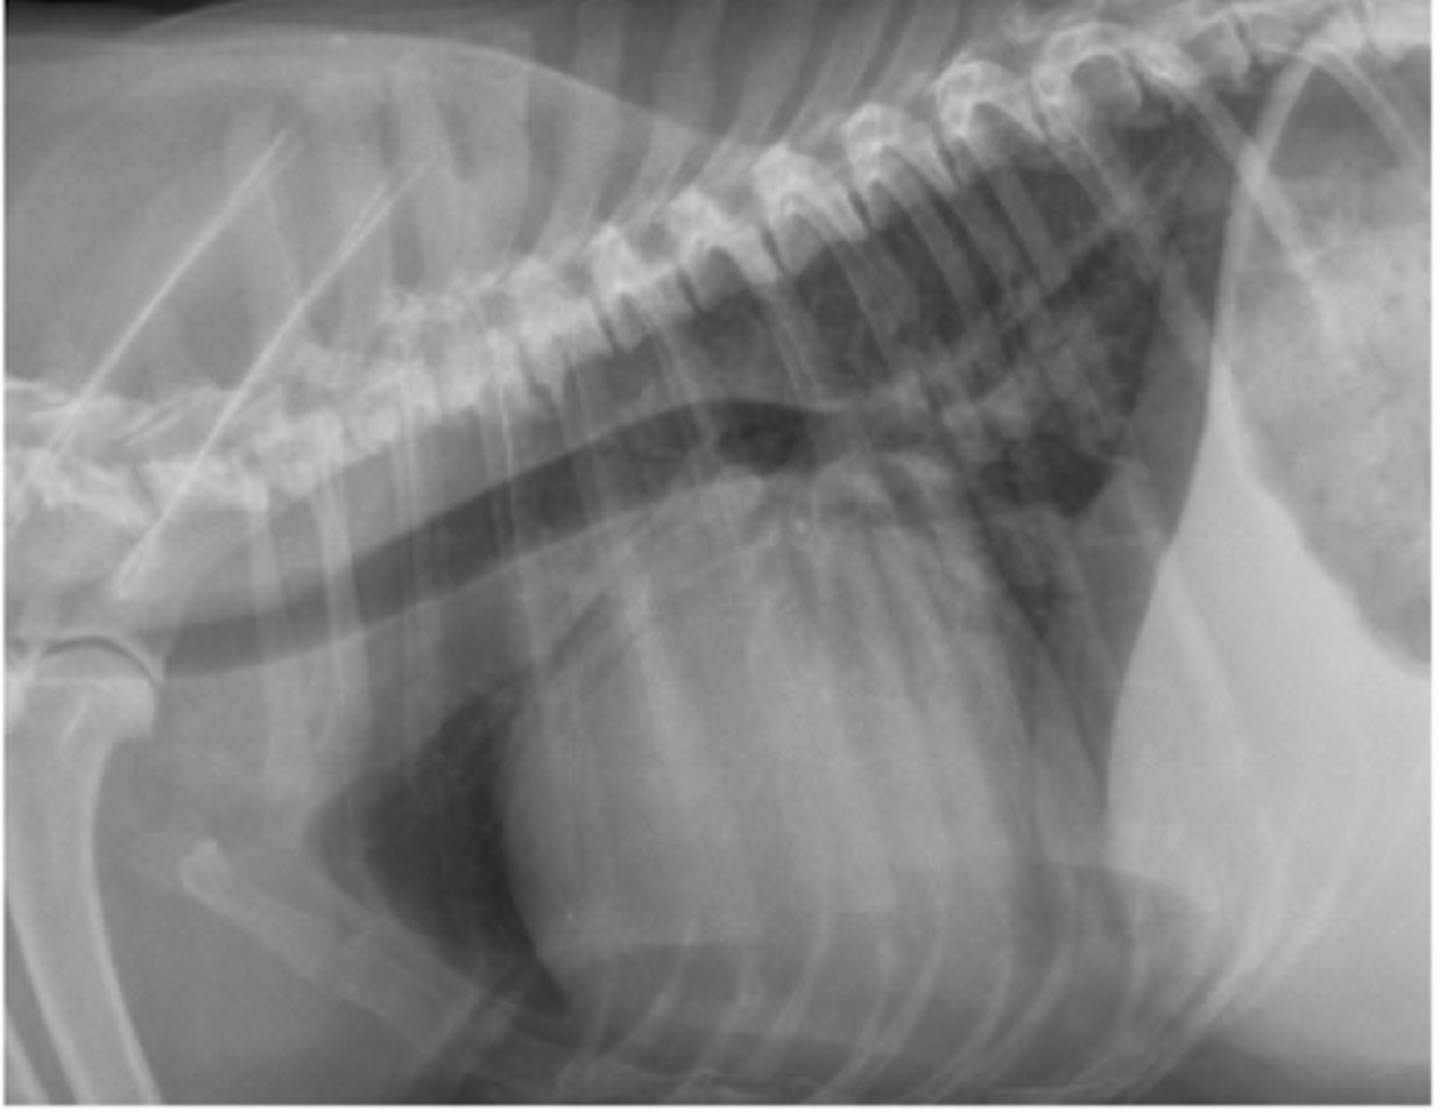

dilatación-torsión gástrica

patología: